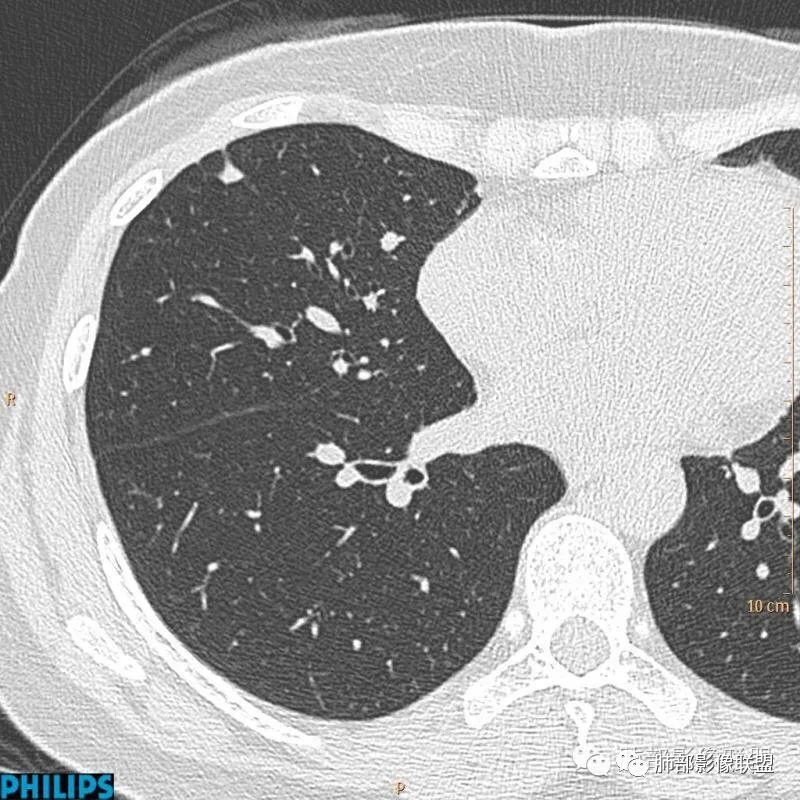

病例一:

以上病例,有什么共同点?1、病灶均位于胸膜下或叶间胸膜下;

2、病灶边缘多平直,大部分呈三角形,部分呈椭圆形;

3、病灶边缘见一条或数条细线与胸膜相连。

正常情况下,肺内淋巴结是不显示的,一般是慢性炎症所致,老年人和吸烟者多见。影像上常见于胸膜或叶间胸膜下,迄今为止,所有的报道均距胸膜或叶间胸膜小于2.0cm以内。也可以表现为与胸膜或叶间胸膜相贴的结节。绝大多数位于中下叶(气管隆突水平以下),上叶也可见到,但较少见。

长径均小于12mm。典型的形状为三角形,也可以为梭形、圆形或椭圆形。诊断的关键在于见到1-5条细线与胸膜、叶间胸膜或静脉相连,有时状如坐落于电路板的“二极管”,但以薄层CT显示为佳。有作者病理对照线状影为小叶间隔,有作者病理对照为淋巴管。其实不矛盾,因为淋巴管走行于小叶间隔内。